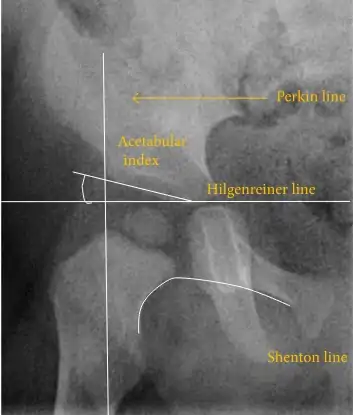

The most useful lines and angles that can be drawn in the pediatric pelvis assessing hip dysplasia are as follows:[3]

- (A) Hilgenreiner line, connects the inferior tips of the iliac bones,[4] at the triradiate cartilage. This line is used to measure the acetabular angle and as a reference for Perkin line.

- (B) Perkin line is perpendicular to Hilgenreiner line, touching the lateral margin of the acetabular roof.[5] This leads to four quadrants and a normal femoral head has to be located in the inferomedial quadrant. We can measure the lateral displacement of the femoral head with regard to the Perkin line by dividing the width of the head that crosses the Perkin line by the diameter of the head. The value for patients under 3 years must be 0 and in older children this ranges from 0 to 22%.

- (C) Shenton line is a continuous arc drawn from the inner edge of the femoral neck to the superior margin of the obturator foramen. In children over about 3 to 4 years of age, this line should be smooth and undisrupted, otherwise it may indicate a fracture or hip dysplasia.[6] However, in infants this line can be unreliable as it depends on the rotation of the hip when the image is taken.[7]

- (D) The acetabular index measures the acetabular roof slope. It is the most useful measure of acetabular dysplasia until 6 years of age. It is formed between Hilgenreiner line and the acetabular roof. In newborns, values of in males and in females are considered normal. It normally decreases with age: